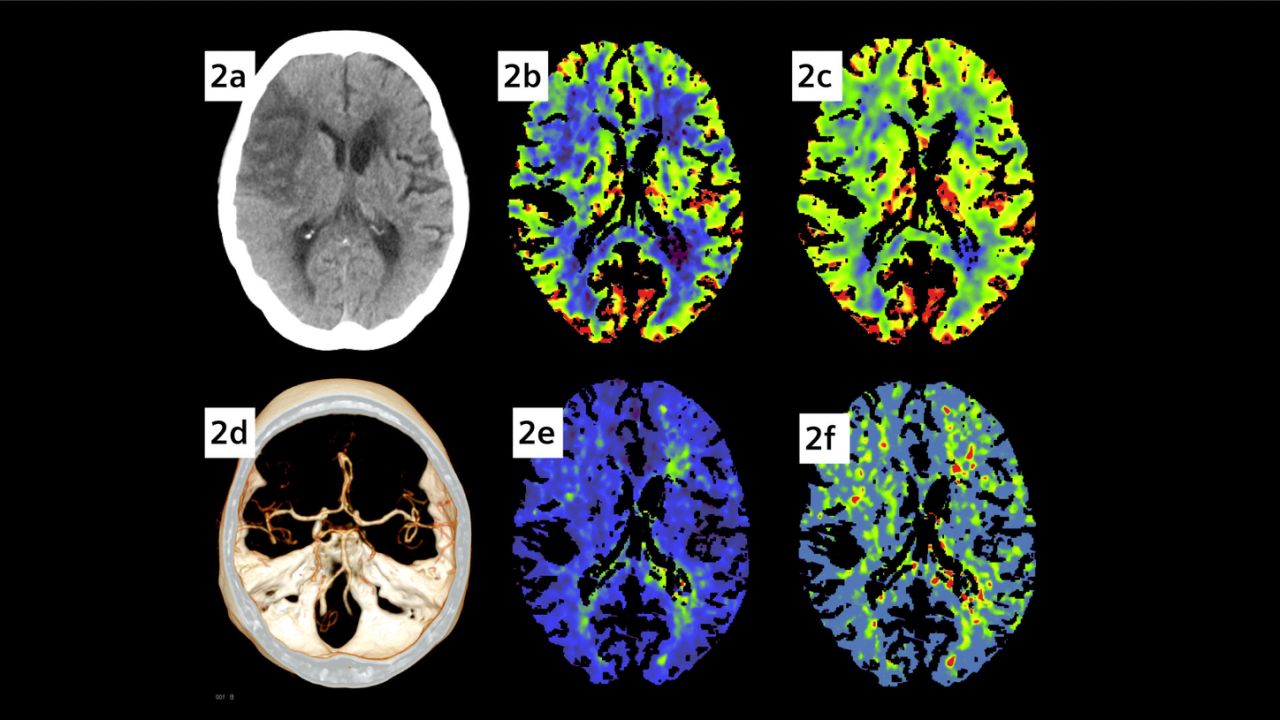

La Enfermedad Vascular Cerebral (embolias, derrames) es seria y discapacitante, cuando ocurre de novo es una emergencia que pone en peligro la función y la vida y existen maneras sencillas de detectarla pues el tiempo es crucial. Me especializo en el diagnóstico, prevención, rehabilitación y tratamiento de dicha patología lo que reduce considerablemente sus costos humanos y económicos, y procuro regresar la calidad de vida al paciente, además de la seguridad de sentirse apoyado por un experto en dicho campo. No me dedico a tratar enfermedades solamente: incido positivamente en la vida de mis pacientes.

Ultrasonido Doppler transcraneal

Estudio no invasivo que puede describirse como "El estetoscopio del Cerebro. " Tiene múltiples aplicaciones en el diagnóstico de las enfermedades de las Arterias Cerebrales, por ejemplo: Hemorragia Subaracnoidea, Traumatismo Craneoencefálico (Flujo Sanguíneo Cerebral), Infarto Cerebral, Diagnóstico de Muerte Cerebral, complicaciones Cerebrovasculares diversas, diagnóstico del Embolismo Cardiaco al Cerebro (ej. Foramen Oval Permeable), Enfermedad de células falciformes. Así como monitoreo preventivo en quirófano para: Neurocirugía Vascular, Terapia Endovascular Neurológica, Cirugía Cervical de Carótidas, Cirugía Cardiaca (en la prevención de Embolia Cerebral).

Infarto cerebral

Una persona tiene alto riesgo de infarto cerebral cuando de un momento a otro no puede: 1) Hablar bien 2) No puede elevar ambas manos a la misma altura (una de ellas cae) ó 3) Su boca se va de lado Esto consituye una emergencia, tan importante como un infarto al corazón. Se requiere acudir a urgencias inmediatamente pues tiempo es cerebro, el médico que idealmente trata algo así es el Neurólogo Vascular. También puede ser atendido adecuadamente por los médicos en Urgencias.